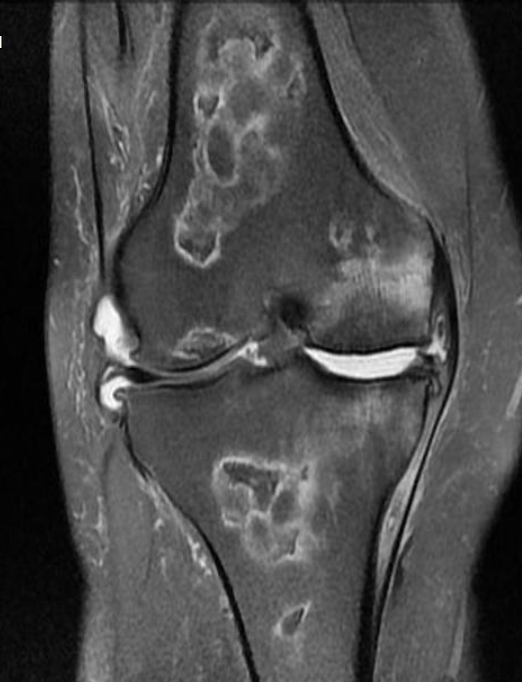

Cisto ósseo aneurismático

Acomete paciente jovem (fise aberta);

Localização excêntrica, aspecto em favo de mel no RX;

Pode ter reforço periosteal;

RM:lesão multicística; Septos + nível liquido-liquido (lesões dx diferencial: COS fraturado, COA, TCG ou osteossarcoma telangiectásico).

Primário ou Secundário à outros tumores: TCG, DF, Condroblastoma.